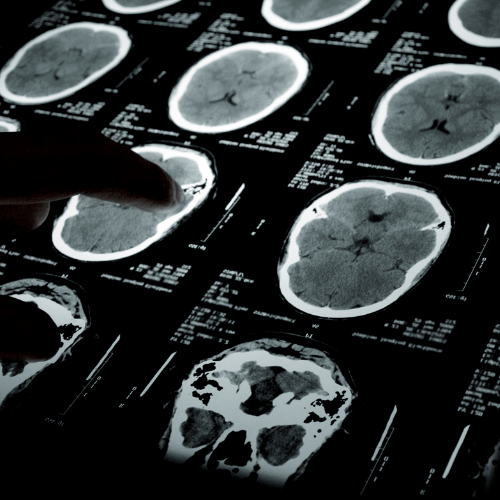

CT Scan vs. MRI: What’s the Difference and When Do You Need Each?

Introduction Medical imaging plays a crucial role in diagnosing and monitoring a wide range of health conditions. Two of the most frequently used diagnostic tools